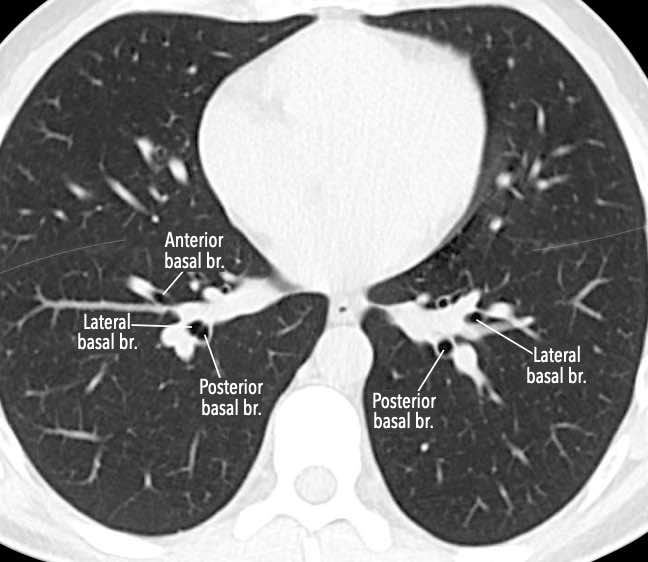

Phế quản trên CT

Cuộn qua các hình ảnh để quan sát khí quản phân chia thành phế quản chính phải và trái, sau đó tiếp tục phân chia thành các phế quản thùy và phế quản phân thùy.